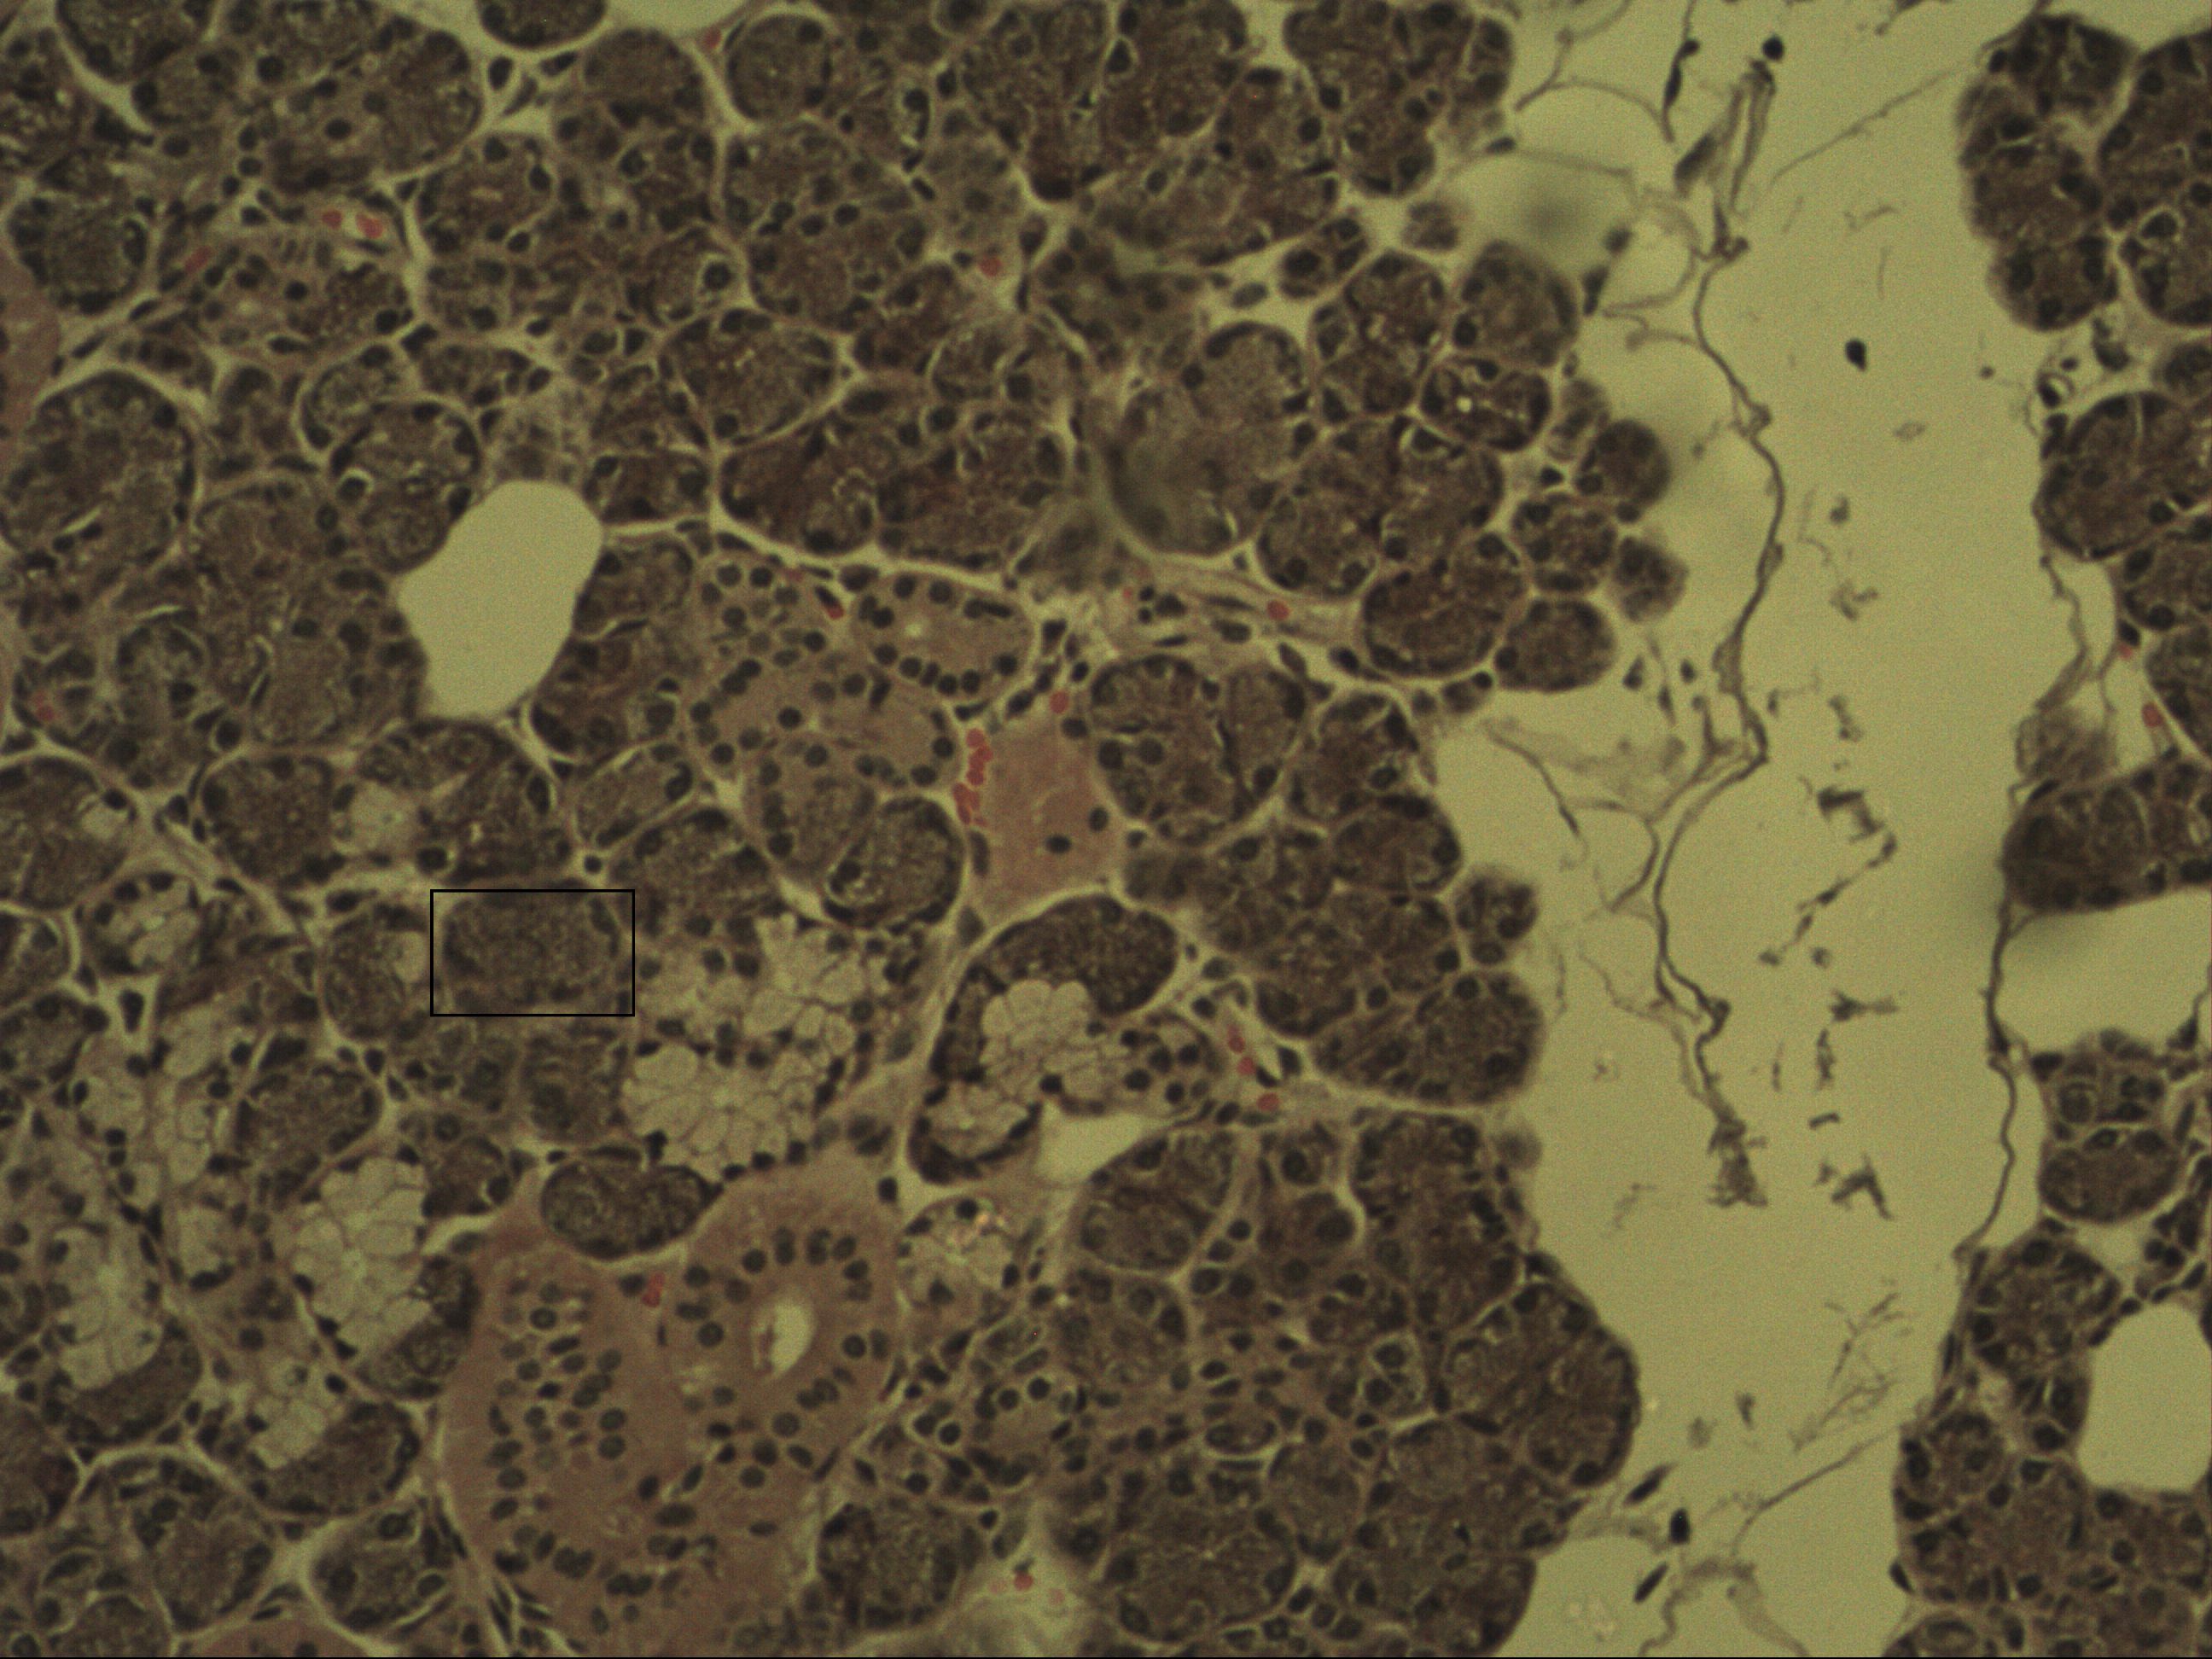

Tubuloazinöse Drüse

Glandula submandibularis [HE]

Hier erkennt man eine gemischte Drüse: Es handelt sich um eine serösmuköse Drüse. Dies bedeutet, dass man mehr seröse anstatt muköse Drüsen vorfindet. Dies lässt sich hier auch Anhand der Entstücke nachvollziehen. Außerdem ist ein Halbmond zu erkennen und ein Ausführungsgang. Ausführungsgänge werden in Schaltstücke und Streifenstücke (größeres Lumen) eingeteilt.